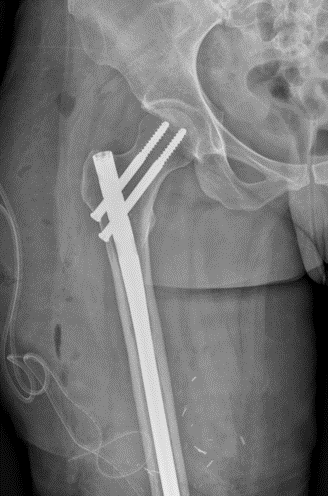

Case presentation: 70 yo F presents to clinic s/p short CMN of left intertroch fx at outside facility in Aug 2022 with worsening left hip pain, inability to bear weight. No pertinent PMHx. Workup and treatment plan?

Infxn workup negative, Lateral approach used, Wagner osteotomy to facilitate nail removal, autograft from femoral/neck 50 cc allograft to graft defect in posterior column, multihole cup/screws w/ dual mobility, modular fluted tapered stem.